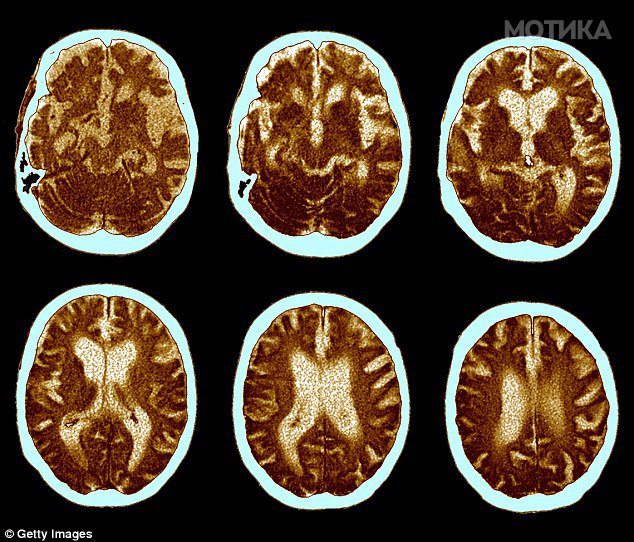

Покрај тоа, умереното пиење пиво штити и од артериосклероза, а кинески научници утврдиле дека состојката ксантохумол која се наоѓа во хмељот може да спречи оксидативно оштетување на мозочните клетки што се поврзува со деменцијата.